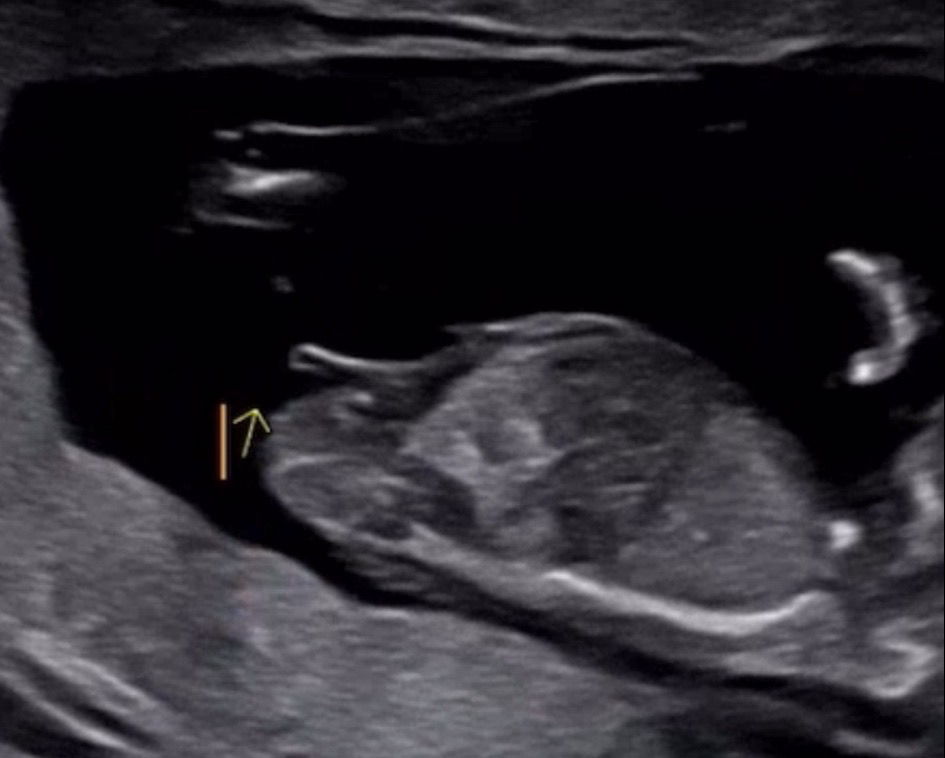

돌기 본 이후로 각도법에만 미쳐있네요.. ㅋㅋ